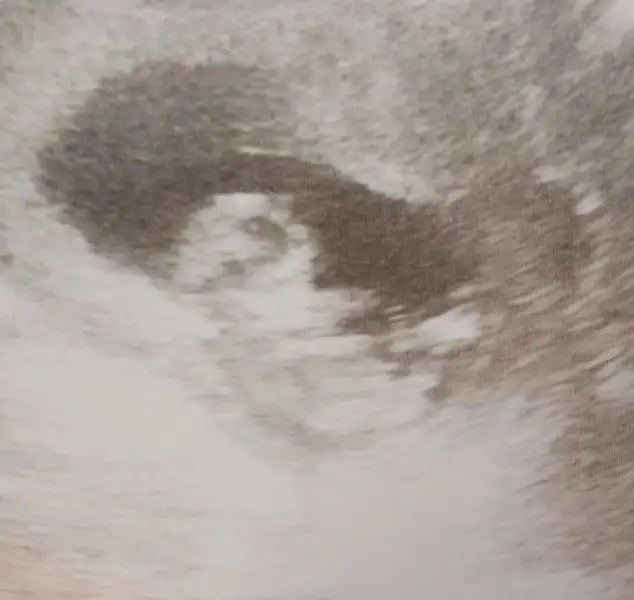

Bebeğin kesedi konumu teorisi tuttum canım sağlıkla kucaklaTahmini olan var mi acaba ? :)

Canım sana zahmet olmazsa bize de bakabilir misin? Soldaki yeni bebeğim sağdaki oğlumun ultrason görüntüsüydüHavalianne__